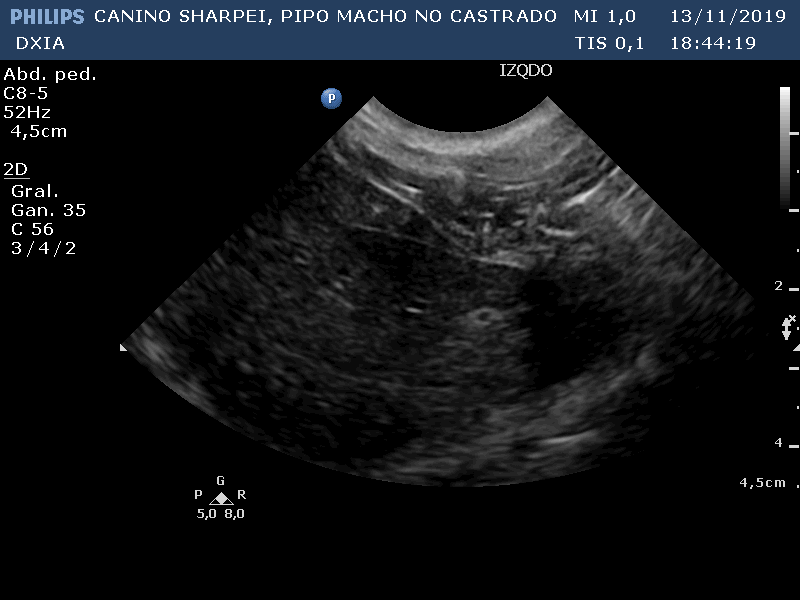

Comentario imágenes A y B: Comparativa Asas ID normal con asa alterada donde se observa aumento de la pared (engrosamiento) con pérdida de estructura en capas.

Neoformación en ID de la que se realiza PAF ecoguiada.